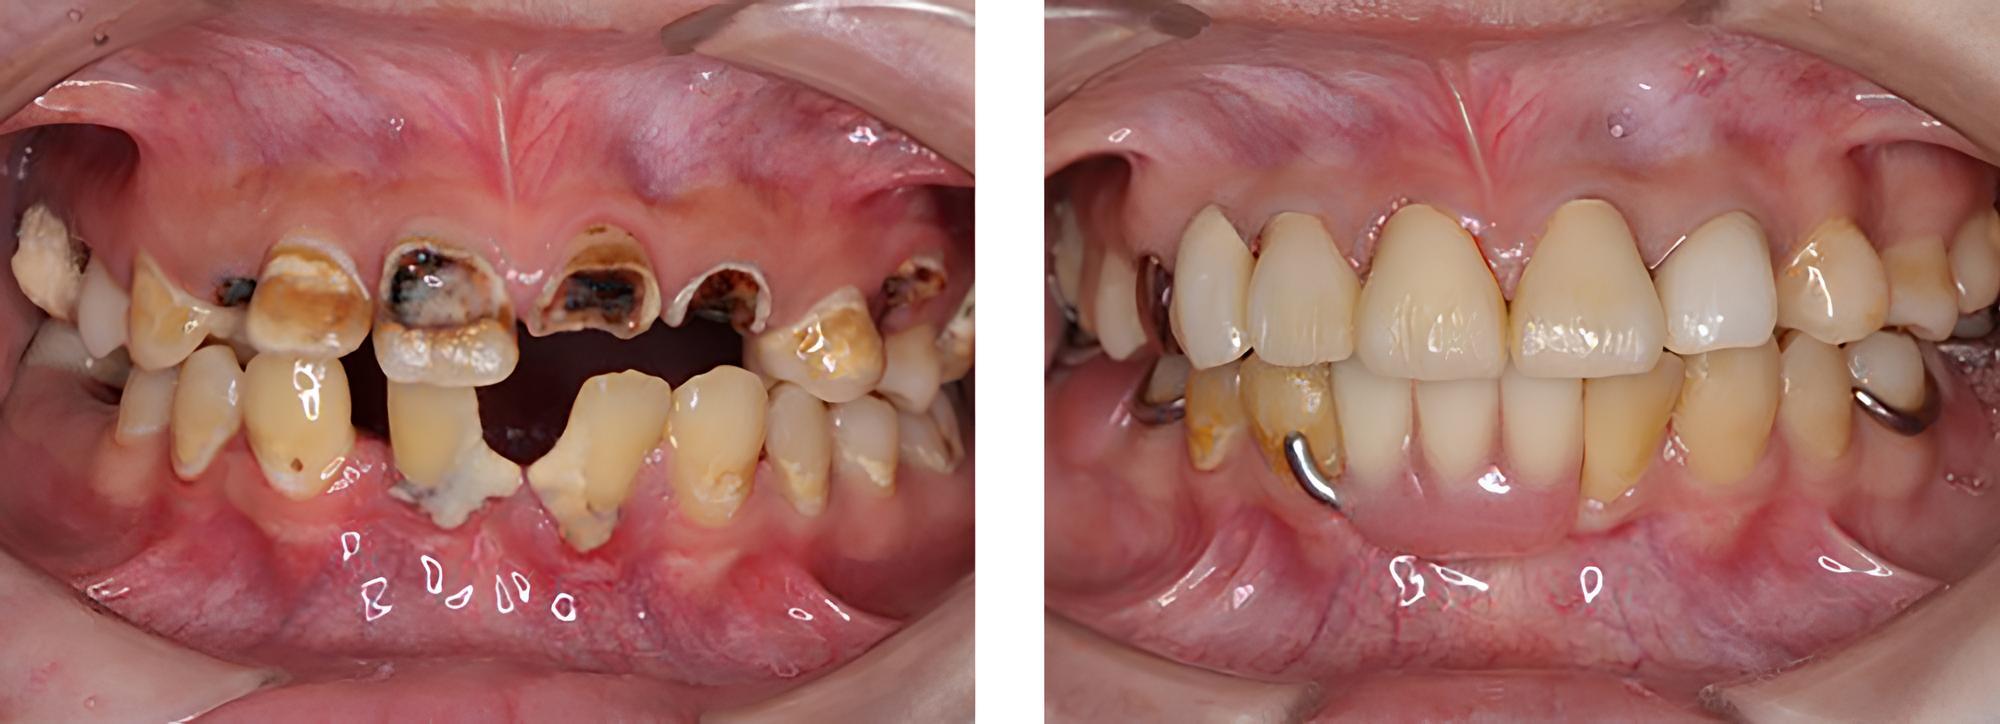

全顎保険治療

術前

術後

| 治療内容 | 全顎的に保険内で治療を行った |

|---|---|

| 治療期間・回数 | 約2.5年・約50回 |

| 費用 | 保険適用となります |

| リスク・副作用 |